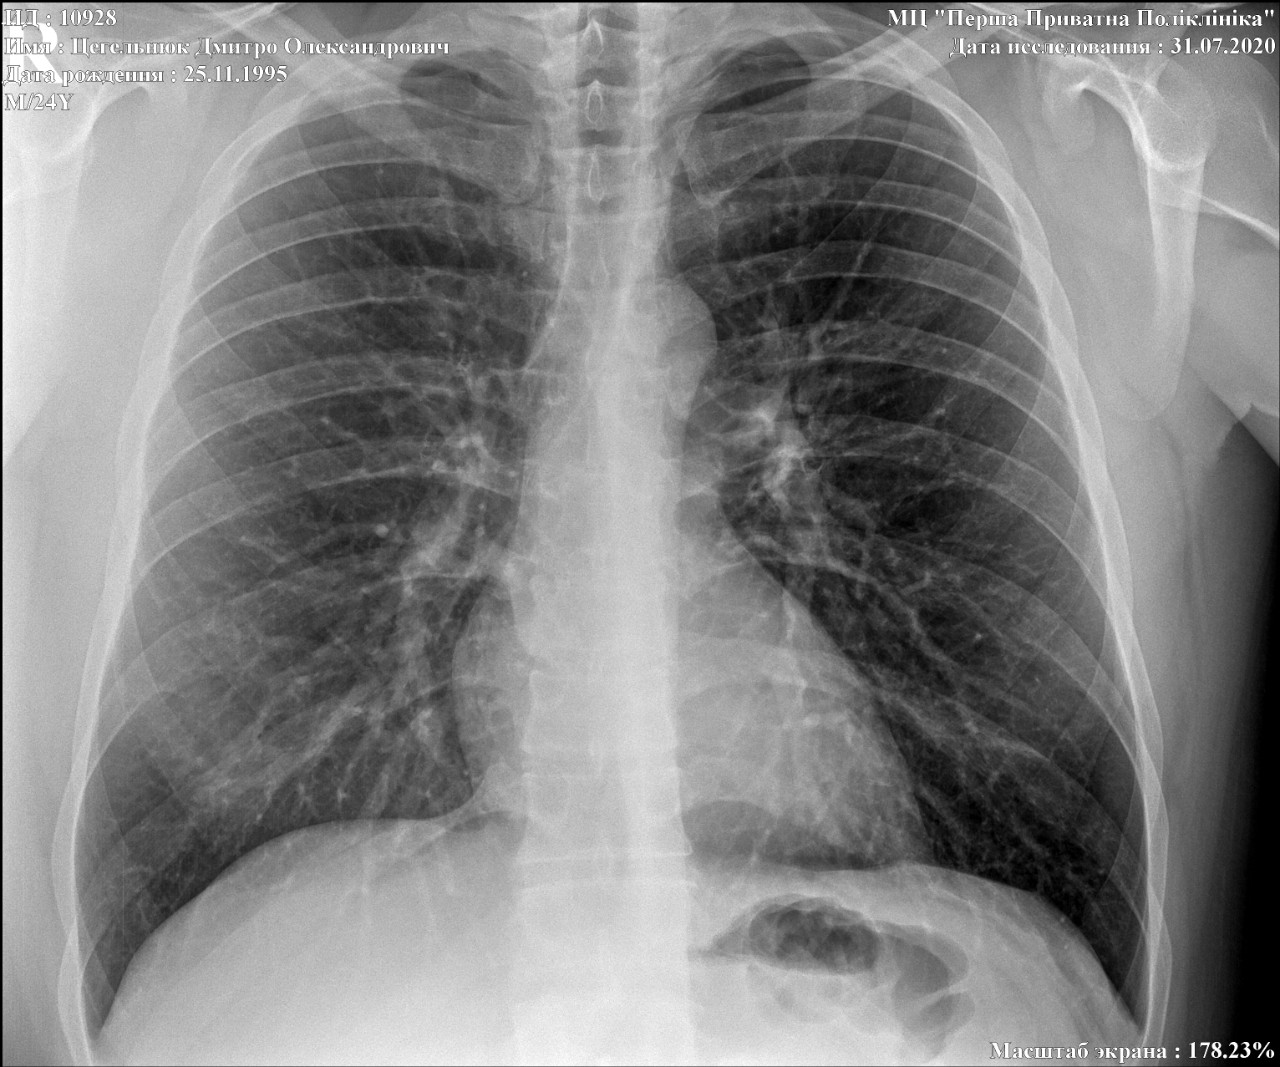

Снимок грудной клетки здорового ребенка: примеры и диагностика

Раздел: Мудрость в объективе